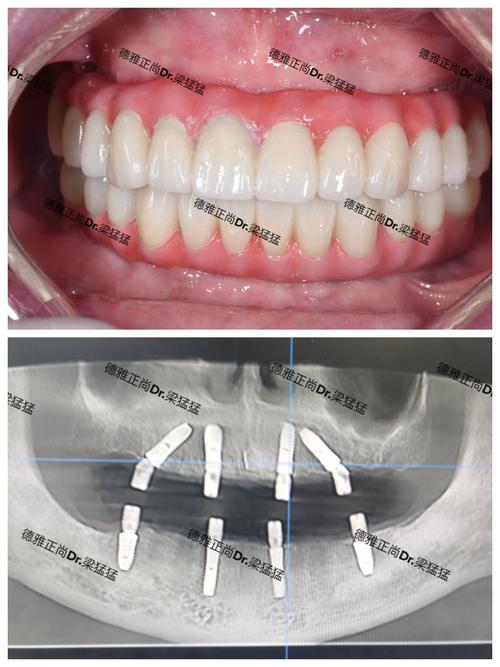

- 数字化种植: 普遍采用CBCT(锥形束CT)进行术前精准评估,利用3D导板技术辅助种植,提高精准度和安全性,减少创伤。

- 即刻种植/即刻负重: 在符合条件的患者中,可以实现当天种牙、当天戴牙(临时冠或永久冠)。

- 设备: 作为连锁机构,一般会配备较先进的口腔设备,如CBCT、口内扫描仪、种植机等,支持数字化诊疗流程。